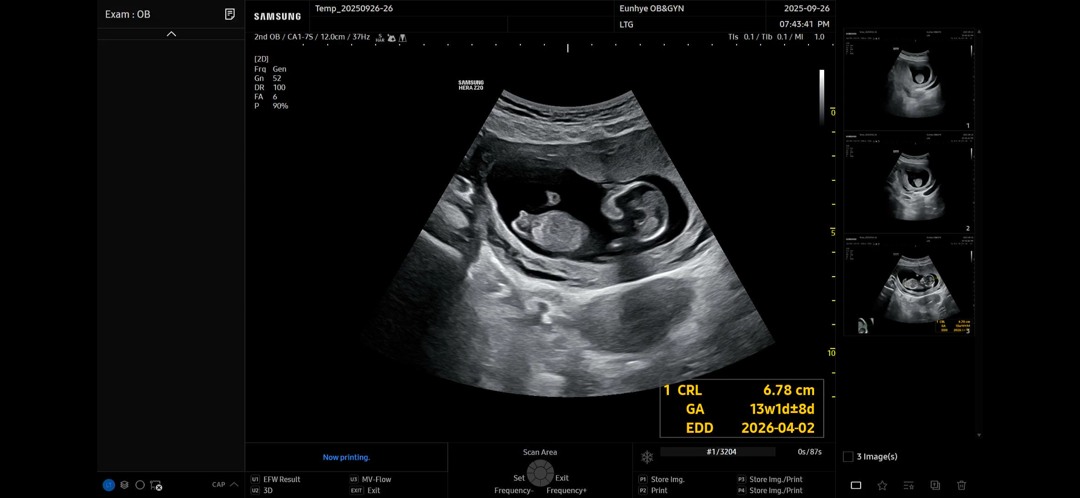

12주5일차 각도법 성별 궁금해요🙏

성별이 너무 궁금해요. 각도법으로 알 수 있나용?